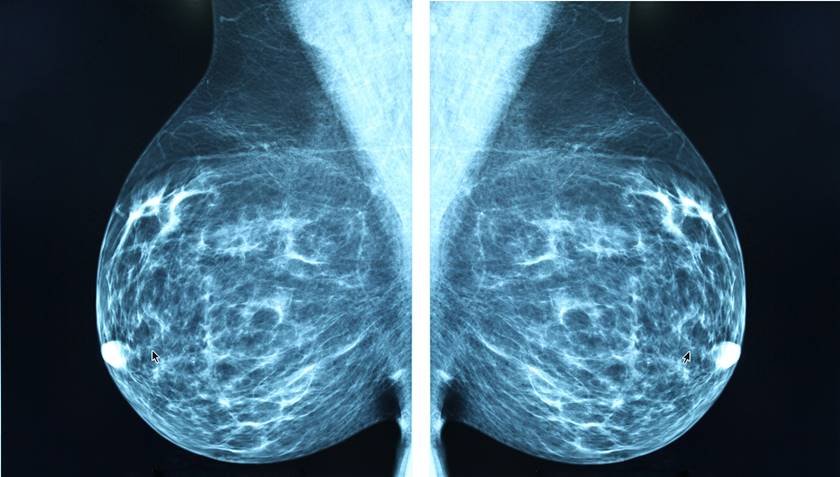

Pesquisadores da Fiocruz (Fundação Oswaldo Cruz) em Minas Gerais conseguiram reeducar células de defesa do organismo para combater o câncer de mama. O estudo abre caminho para desenvolver novos tratamentos de imunoterapia, ou seja, que estimulam o próprio sistema imunológico a reconhecer o tumor como algo a ser destruído.Para chegar a esse resultado, os cientistas usaram nanopartículas de óxido de ferro, que são estruturas muito pequenas capazes de uma grande interação com as células e com baixa toxicidade. O objetivo era modificar um tipo de célula de defesa, os macrófagos, para que elas pudessem combater o câncer. Essas células compõem quase metade da massa de um tumor.Enquanto um tipo de macrófago, o M1, ajuda a limitar o crescimento das células cancerosas porque tem características inflamatórias, o tipo M2, ao contrário, tem ação anti-inflamatória e permite o crescimento das células tumorais. As nanopartículas introduzidas nas células alteram a quantidade de ferro presente e fazem uma reprogramação celular. Assim, elas transformam o M2 em M1.Os cientistas fizeram o estudo em 3 etapas: primeiro testaram o efeito in vitro, cultivando macrófagos e células tumorais em laboratório. Em contato com as nanopartículas, eles conseguiram fazer a reprogramação dos macrófagos e provocar a morte das células indesejadas. Depois, foi feito um ensaio em um modelo 3D multicelular, que imita o microambiente do tumor do câncer de mama, incluindo outras células do organismo humano.Por fim, foram feitos testes em camundongos com câncer de mama. “Foi o resultado mais surpreendente porque, com apenas uma aplicação, conseguimos reduzir em 50% a massa tumoral”, conta Camila Sales Nascimento, pós-doutoranda do grupo de Imunologia Celular e Molecular, uma das líderes do trabalho.As nanopartículas de óxido de ferro usadas no estudo foram produzidas nos laboratórios da Fiocruz Minas, por meio de uma parceria com a equipe do professor Celso Melo, do Departamento de Física da Universidade Federal de Pernambuco, que desenvolveu, originalmente, o composto.Nova opção de tratamento

Pesquisadores da Fiocruz (Fundação Oswaldo Cruz) em Minas Gerais conseguiram reeducar células de defesa do organismo para combater o câncer de mama. O estudo abre caminho para desenvolver novos tratamentos de imunoterapia, ou seja, que estimulam o próprio sistema imunológico a reconhecer o tumor como algo a ser destruído.Para chegar a esse resultado, os cientistas usaram nanopartículas de óxido de ferro, que são estruturas muito pequenas capazes de uma grande interação com as células e com baixa toxicidade. O objetivo era modificar um tipo de célula de defesa, os macrófagos, para que elas pudessem combater o câncer. Essas células compõem quase metade da massa de um tumor.Enquanto um tipo de macrófago, o M1, ajuda a limitar o crescimento das células cancerosas porque tem características inflamatórias, o tipo M2, ao contrário, tem ação anti-inflamatória e permite o crescimento das células tumorais. As nanopartículas introduzidas nas células alteram a quantidade de ferro presente e fazem uma reprogramação celular. Assim, elas transformam o M2 em M1.Os cientistas fizeram o estudo em 3 etapas: primeiro testaram o efeito in vitro, cultivando macrófagos e células tumorais em laboratório. Em contato com as nanopartículas, eles conseguiram fazer a reprogramação dos macrófagos e provocar a morte das células indesejadas. Depois, foi feito um ensaio em um modelo 3D multicelular, que imita o microambiente do tumor do câncer de mama, incluindo outras células do organismo humano.Por fim, foram feitos testes em camundongos com câncer de mama. “Foi o resultado mais surpreendente porque, com apenas uma aplicação, conseguimos reduzir em 50% a massa tumoral”, conta Camila Sales Nascimento, pós-doutoranda do grupo de Imunologia Celular e Molecular, uma das líderes do trabalho.As nanopartículas de óxido de ferro usadas no estudo foram produzidas nos laboratórios da Fiocruz Minas, por meio de uma parceria com a equipe do professor Celso Melo, do Departamento de Física da Universidade Federal de Pernambuco, que desenvolveu, originalmente, o composto.Nova opção de tratamento